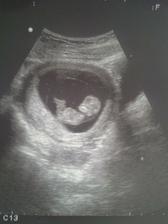

20.5.2010...tak už máme fotekčku,nechala jsem si ji udělat asi v 10tt,je krásná. Naše bambulka nebo bambulák sebou pěkně mrskal,kopal nožičkama-naštěstí to ještě necítím,ručičkama boxoval, pak se nám chtěl schovat,ale sestřička byla pohotová a udělala nám krásnou fotečku jak se na nás bambulátko směje. 14.5.2010 jsem byla na cukr testech,pěknej hnus, první půl hodinu mi bylo pěkně zle, ale než jsem šla na druhý odbběr krve tak už mi bylo líp. Pak už jsem jen čekala celou hodinu na poslední odběr a hurá honem si něco koupit do žaludku. Jinak těhu probíhá zatím bezproblémově, bříško pomalu roste, chutě zatím na nic konkrétního nemám. Čeká mě první poradna a UZ. Teď pomalu končím 13tt.